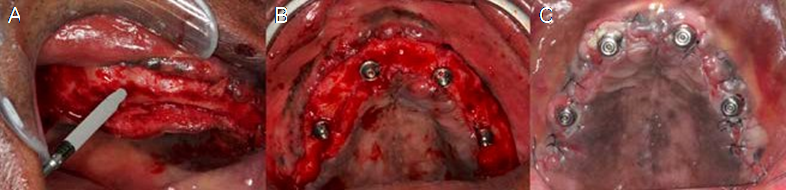

After anesthesia of the upper jaw, an incision was performed in the bone crest followed by a buccal and palatal detachment of a flap from the right molar to the left molar. Horizontal osteotomy was performed to avoid esthetics and functional problems. The implant sites preparation was carried out according to the manufacturer's instructions. Perforations were initiated by the initial drill, followed by the drills 2.0mm, 3.5mm, 2.8/3.5mm and 3.75mm, with undersized site preparation technique. Two 3.75 x 20mm GM Helix Long Neoporos implants (Neodent, Curitiba, Brazil) were placed in the regions of teeth #15 (Figure 3.A) and #25 and two 3.75 x 13mm GM Helix Acqua implants (Neodent) in the regions of teeth #12 and #22. The four implants were placed 2mm subcrestally and anchored apically in the region of the paranasal bone with an insertion torque of 60 N.cm.

Due to the high initial implant stability obtained, it was possible to apply the immediate loading technique. Two GM Mini Conical Abutments of 30 degrees with 2.5mm transmucosal height (Neodent) were used on the implants of sites #15 and #25 and two GM Mini Conical Abutment of 17 degrees with 2.5mm transmucosal height (Neodent) were used in implants of sites #12 and #22 (Figure 3.B). The upper arch was sutured with 5.0 resorbable suture thread. Then, four open-tray impression copings were placed on the abutments and joined to the multifunctional guide in occlusion with the lower arch using Pattern acrylic resin (GC America Inc, Alsip, USA). The impression was performed with condensation silicone Speedex (Coltene, Altstätten, Switzerland) and sent to the prosthesis laboratory.

A passive fit technique was used to fabricate the prostheses. The mini abutment analogs (Neodent) were positioned in the transfers that were held in the impression material, and the definitive cast was obtained with artificial gingiva in place. Subsequently, the brass copings of the passive fitting technique (Neodent) were screwed to the analogs, and the castable coping was adapted over the brass ones. The framework was waxed and then soldered and adapted onto the brass copings of the working cast. The prosthetic teeth were mounted according to the intraoral clinical evaluation. The prosthesis was processed. The brass copings were removed and titanium copings (Neodent) were screwed into the working cast. The access holes were sealed, and the framework was cemented over the titanium copings with an adhesive resin cement (Panavia; Kuraray America Inc.) (11). This technique compensates for any distortion inherent in 1-piece castings by luting the framework to the titanium cylinder, which has a smalle dimension than the brass coping used during the framework waxing (12). The prosthesis was finished. Although it was screw retained, a precise fit was achieved because the cement compensated for any casting distortions. After 24 hours, the patient returned with good healing of the upper arch (Figure 3.C) and a try-in of the teeth fixed with wax to the metal bar was performed.